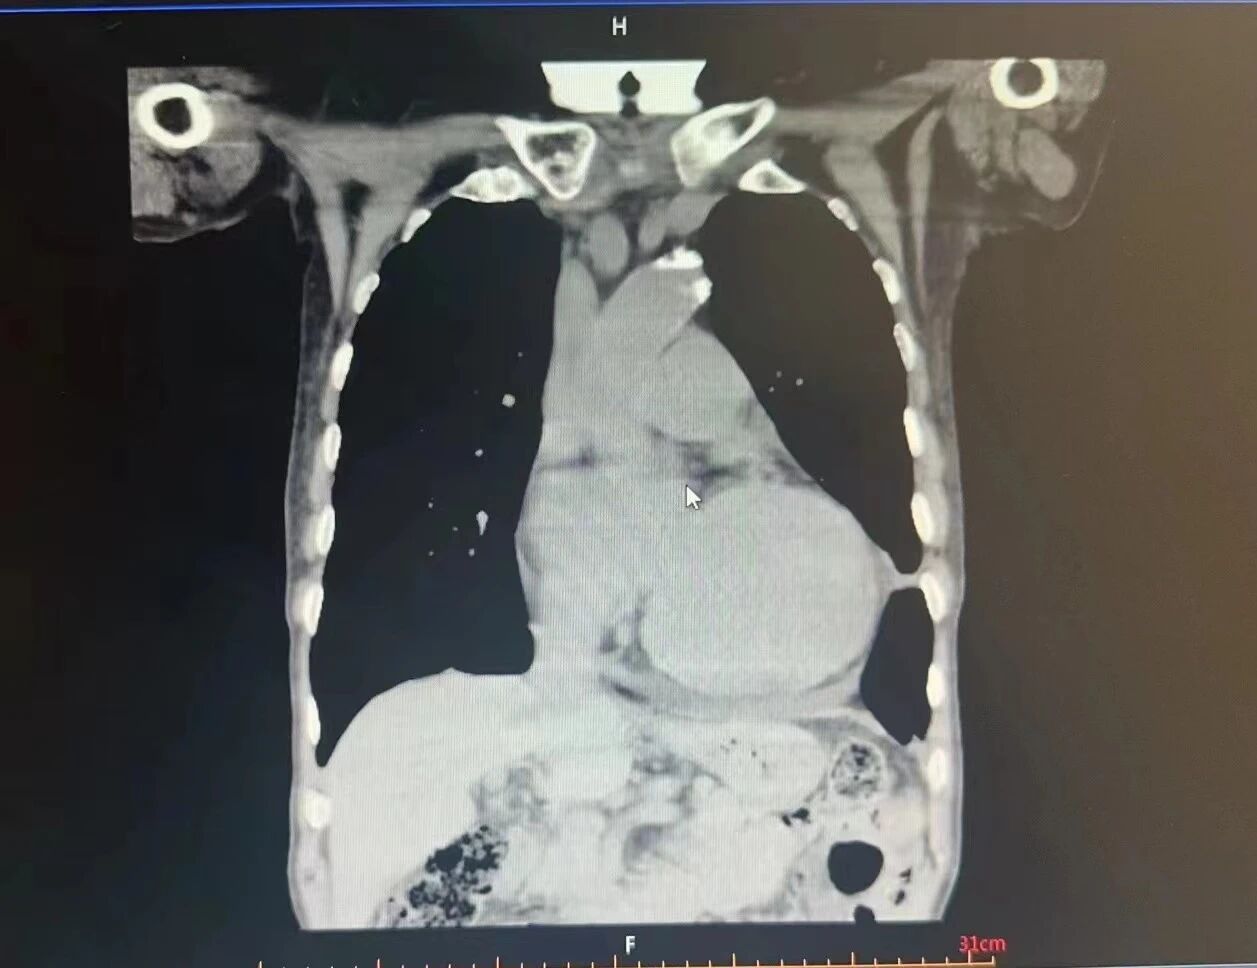

患 者 术 前 胸 部CT

2、胸部CT:(1)双肺多发结节,转移瘤?请结合临床;(2)右肺上下叶及左肺渗出,双侧胸腔少量积液;(3)左侧上叶少许间隔旁型肺气肿;(4)心脏增大,肺动脉增粗,心包少量积液;(5)右侧第7及左侧第3、4肋、胸骨改变,转移?请结合临床。